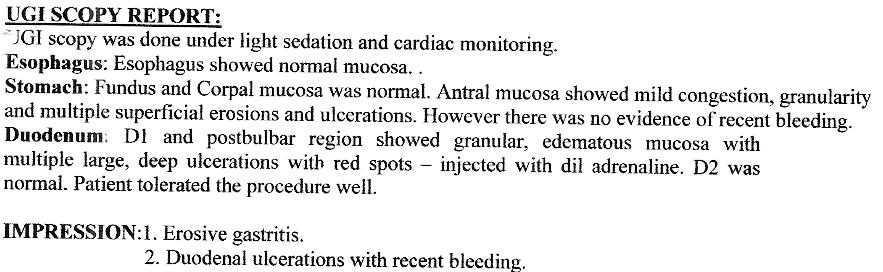

Duodenum - Chronic Ulcer

Duodenum - Chronic Ulcer with Bleeding

Vomiting of blood due to ulcer, narrowing of duodenum due to ulcer or cancer can be very effectively treated by gastroscopy.